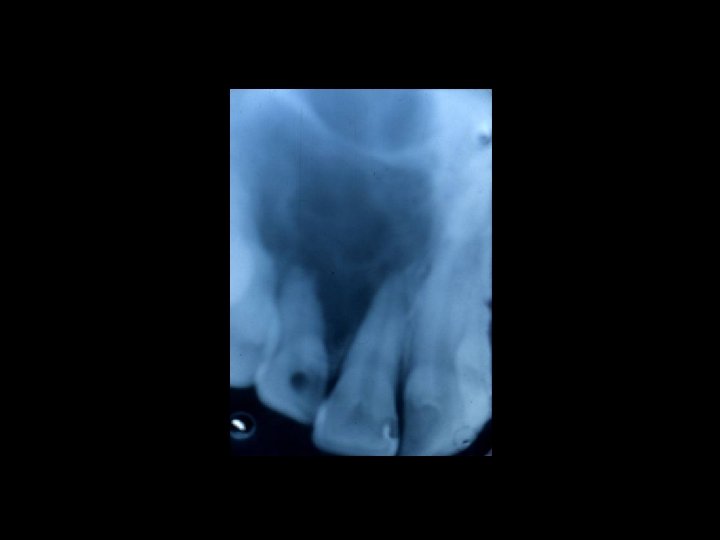

Responsabilità Ø Restauro della corona del dente Ø Trattamenti radicolari